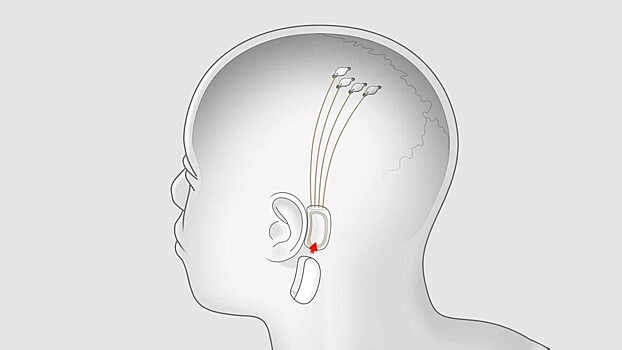

Проект Neuralink, основанный Илоном Маском, по неизвестной причине покидает сооснователь Макс Ходак (Max Hodak). Эта компания известна разработкой мозговых чипов. Недавно она показала ролик с макакой, которая играет в видеоигры благодаря вживлённому в мозг чипу.